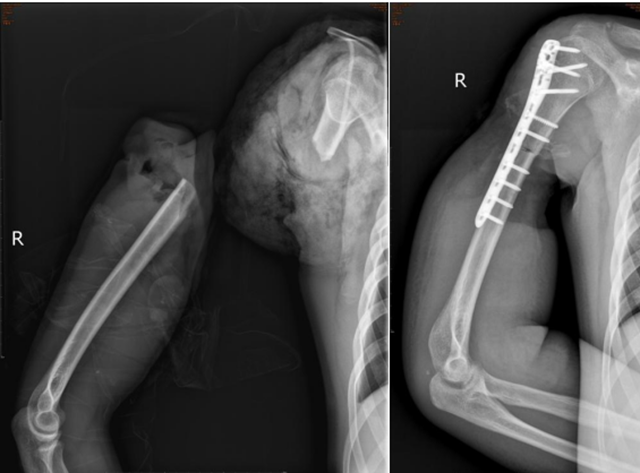

2023年9月的某一天,19歲的李明(化名)在沙石廠干活時,被“輸送機皮帶”絞傷右上肢,當即致右上臂處完全離斷,疼痛劇烈、出血不止。

工友立即撥打120,由120將李明送至西南醫(yī)科大學(xué)附屬中醫(yī)醫(yī)院急診科,急診以“右上臂創(chuàng)傷性切斷”收入骨傷科手外·兒骨·燒傷整形組。

值班醫(yī)生王波接診處理后,科室副主任陳孝均、醫(yī)療組長劉安銘、主治醫(yī)師黃宇、主管醫(yī)生王波共同為患者制定了急診手術(shù)方案:右上臂斷肢再植+血管移植術(shù),手術(shù)歷時8小時。

術(shù)中及術(shù)后予以輸血、抗感染、抗血管痙攣、補液擴容等治療,后期又歷經(jīng)清創(chuàng)、植皮等多次手術(shù),最終為李明保住了右上肢,留住了一個青年人的希望。